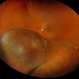

- Choroidal melanoma, brachytherapy, collar button

- 52 year old female at first visit July 2023 vs 7 months s/p brachytherapy. SRF in macula has resolved, trace fluid on posterior edge of collapsing collar button.